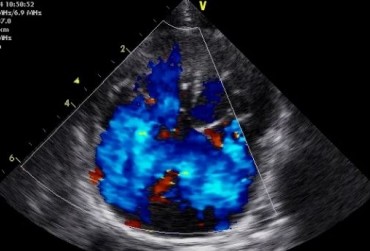

Dysplazja zastawki trójdzielnej i zespół Wolffa–Parkinsona–White’a u kota – opis przypadku

Zwężenie zastawki trójdzielnej jest jedną z form dysplazji pojawiającą się w różnym stopniu nasilenia (najczęściej łącznie z niedomykalnością zastawki) zarówno u psów, jak i u kotów. Cechami charakterystycznymi definiującymi zwężenie zastawki trójdzielnej są: obecność rozkurczowego wybrzuszenia (doming) płatków zastawki, zmniejszona ruchomość płatków, zmniejszona średnica ujścia zastawki. Mimo że zmiany morfologiczne aparatu trójdzielnego są typowe w przebiegu TVD i są znakiem rozpoznawczym tej choroby, nie są one zawsze bardzo silnie wyrażone i nie zawsze można mieć bezsprzeczną pewność diagnostyczną, bazując na badaniu echokardiograficznym [10]. Przypadki takie zdarzają się przede wszystkim u pacjentów, u których nie postawiono diagnozy we wczesnym etapie życia, a którzy pojawiają się na badaniu dopiero w starszym wieku z zaawansowanymi zmianami i niejednokrotnie z klinicznymi objawami prawostronnej niewydolności mięśnia sercowego i towarzyszącymi zaburzeniami w rytmie. W takich przypadkach obraz choroby może przypominać arytmogenną kardiomiopatię prawokomorową (arrhythmogenic right ventricular cardiomyopathy – ARVC) [1, 8]. Preekscytacja jest często obserwowana u ludzi z anomalią Ebsteina. U zwierzat, podobnie jak u ludzi, obecność dodatkowej drogi przewodzenia może nigdy nie prowadzić do rozwoju tachykardii nadkomorowej lub arytmia ta pojawiać się może dopiero w późniejszym okresie życia. Opisany przypadek jest przykładem pacjenta z dysplazją zastawki trójdzielnej i prawostronną niewydolnością serca będącą najprawdopodobniej konsekwencją tachykardii nadkomorowej.